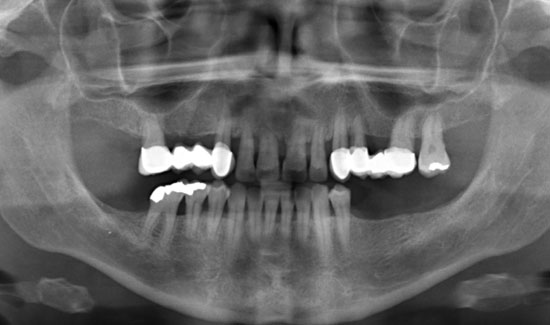

Abb. 1: Orthopantomogramm

Die Patientin stellte sich in unserer Praxis vor mit der Frage der konservativen Erhaltbarkeit der Oberkieferfrontzähne bei chronischer Parodontitis. Wir fanden generalisierte Taschenbildungen (> 10 mm), Spontanblutungen und einen Lockerungsgrad 2/3, d.h. extraktionswürdige Zähne. Als Überbrückungsmaßnahme (Feiertagssituation) bis zu Sanierungsmaßnahmen boten wir ihr lokale Ozongasbehandlungen an.

Als Ozongasspender verwendeten wir Prozone, das mit Hilfe von Kunststoffansätzen Ozongas schmerzarm in die Taschen einzuleiten erlaubt. Die lokale Ozongas-applikation wurde dreimal im Wochenabstand wiederholt. Außerdem wurde die Patientin auf notwendige persönliche Hygienemaßnahmen aufmerksam gemacht. Wir konnten nicht nur die Blutungen stoppen, sondern den Lockerungs-grad der Zähne in einem stabilen Zustand (2) halten und die messbare Taschentiefe verringern.